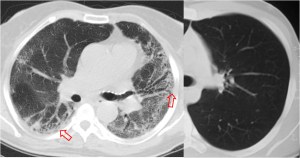

SIGNO DEL CASQUETE APICAL IZQUIERDO

La aparición de una densidad en el ápex pulmonar izquierdo, de borde inferior cóncavo y bien delimitado (casquete apical) en un paciente con traumatismo torácico, debe hacernos sospechar la existencia de una rotura aórtica.

Deben excluirse otras causas de casquete apical, especialmente las lesiones residuales tuberculosas, que suelen acompañarse de otros hallazgos como tractos fibrosos pleuro-parenquimatosos, pérdida de volumen en el lóbulo superior, granulomas, etc.

Mostramos un caso de rotura aórtica por accidente de moto. En este paciente también aparece el signo de la alteración del contorno aórtico.

En el corte de TC de tórax con contraste intravenoso del mismo paciente vemos la rotura aórtica (flecha verde), un hemotórax bilateral –algo más cuantioso en el hemitórax izquierdo- (flechas azules) y un hematoma mediastínico (flecha naranja).